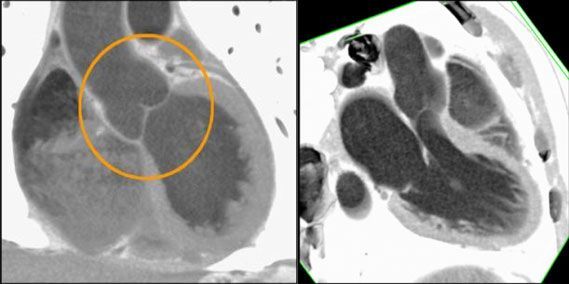

3. острые коронарные синдромы, инфаркты миокарда без подъема ST для оценки поражения венечных артерий сердца [16]. МСКТ позволяет диагностировать возможные осложнения при инфаркте миокарда, к примеру, разрыв межжелудочковой перегородки (рис № 2) [56], а так же развитие аневризмы левого желудочка (рис № 3).

![]() |

| Рис.2. МСКТ сердца. Аневризма в области верхушки левого желудочка (стрелка), кальциноз коронарных артерий. |

| Рис.3. МСКТ сердца. Разрыв межжелудочковой перегородки при остром инфаркте миокарда (стрелка). |